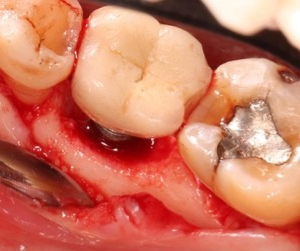

Flap surgery (Gingival surgery)

This procedure cleans deep pockets of infection and helps prevent tooth loss. It is used in advanced cases of periodontitis.